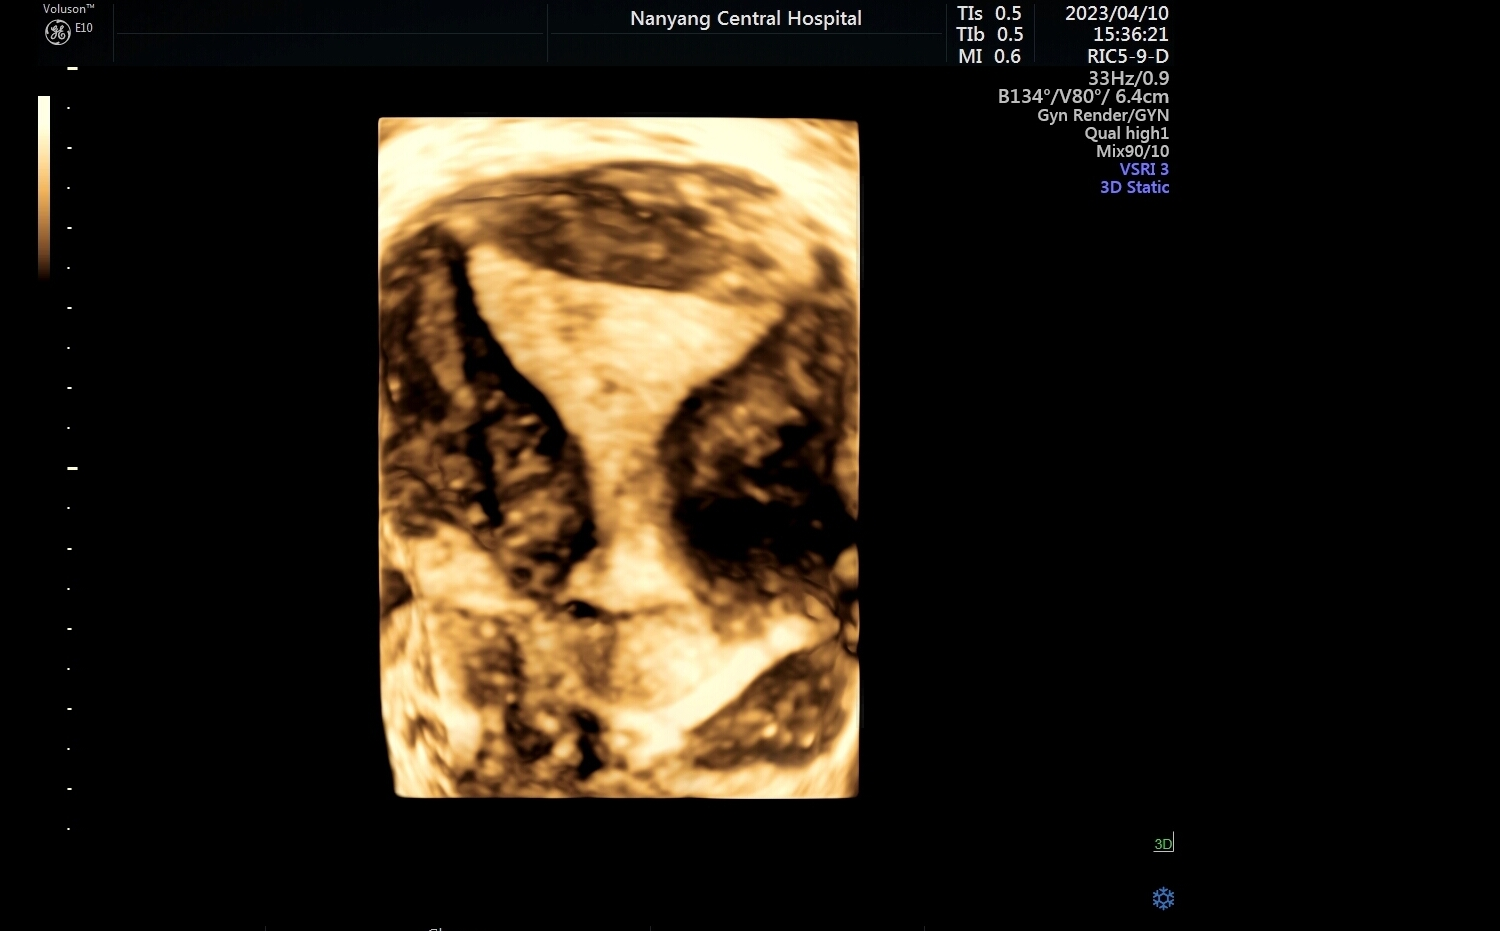

不管是黑白超还是彩超,我们看的图像都是平面的,也就是二维的,超声医师是通过二维切面来观察器官内部的结构。除了基础的二维成像,还有三维、四维重建成像,就是将无数个二维切面组合起来形成一个立体图像,可以更直观、更形象的观察目标结构。

子宫四维图像